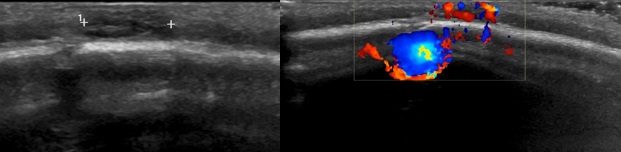

Paciente mujer sin antecedentes familiares ni personales de interés. Embarazo controlado y correctamente suplementado con ecografías prenatales normales. Parto eutócico a las 40+1 semanas con peso recién nacido de 2990 g (p25). No precisa reanimación al nacimiento. Cribado neonatal sin alteraciones. Seguimiento según programa de niño sano en su centro de salud. A los 6 meses se detecta en exploración física plagiocefalia, fontanela anterior de 1,5 × 1,5 cm y a nivel posterior de esta en sutura coronal se visualiza lesión nodular de consistencia blanda redondeada de 0,5 cm de diámetro con coloración violácea. La paciente presenta adecuado desarrollo psicomotor y crecimiento del perímetro craneal. Dada la localización se solicita radiografía craneal y ecografía transfontanelar y de partes blandas. En la radiografía no se visualizan lesiones a nivel óseo y la ecografía transfontanelar no muestra alteraciones. La ecografía de la lesión muestra una imagen nodular, bien delimitada, ovoidea de 6,9 × 3 mm, con hiperseñal Doppler color y ubicada a nivel subcutáneo (Fig. 1), compatible con hemangioma infantil. Se acuerda con los padres actitud expectante y seguimiento periódico en consulta.

| Figura 1. A la izquierda se visualiza imagen nodular, bien delimitada de morfología ovoidea. A la derecha se detecta la hiperseñal Doppler de la lesión |

El hemangioma infantil es una patología frecuente en las consultas de Atención Primaria de Pediatría. Su diagnóstico y seguimiento en muchos de los casos podrá realizarse desde la consulta, sin necesidad de pruebas complementarias, ni derivación a Dermatología. En ocasiones, el diagnóstico puede plantearnos dudas y serán de utilidad las pruebas complementarias, especialmente la ecografía, como ocurre en nuestro caso.